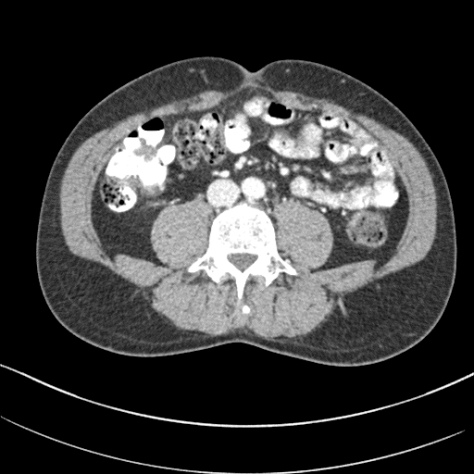

Fig. 3 visualizes sample abdominal CT images with varying quality levels from the test set. The predicted IQA scores show strong agreement with the reference scores across different noise and artifact intensities, which indicates the robustness of CAP-IQA in accurately quantifying CT image quality. The kernel density plot in Fig. 4 illustrates how prediction residuals are distributed across different IQA score groups. All curves are centered near zero, indicating balanced predictions without systematic bias toward any specific quality range. Moreover, the box plot presents the distribution of absolute prediction errors across different IQA score groups. The median errors remain low and consistent, showing that CAP-IQA performs reliably across all quality levels, with minimal variations and stability in predictions. Consistent with this interpretation, our pairwise testing using the Kruskal-Wallis H-test further confirms that there is no significant difference in performance for different IQA score groups (p-value 0.38).

4.8 Real Clinical Evaluation

We also evaluated the proposed CAP-IQA model on an in-house dataset. Fig. 8 displays sample images from the dataset. We retrospectively collected real clinical CT images from the University of Kentucky Medical Center with approval from the Institutional Review Board. A total of 91,514 image slices from 336 pediatric patients aged 2-12 years were used for testing the generalizability of CAP-IQA. Since these images have already been used for clinical diagnosis, they are expected to be of high quality (>3, as per the IQA scoring criteria in Table 1). Slice-wise IQA scores predicted by the model were averaged to obtain the overall score for each of the CT scans. The average IQA score across the 336 pediatric scans is 3.8582, with a correlation of variation of 2.1447. As seen in Fig. 9, the predicted scores are tightly grouped around the mean, with scores above the diagnostic-quality threshold of 3. The relatively high predicted scores align with expert radiologists’ assessments, indicating that the scans retain good diagnostic quality. Overall, the results demonstrate that CAP-IQA performs reliably in real-world clinical settings, and the model consistently and accurately assesses quality across diverse patient data.

![]() |

| 3.95 | 3.71 | 3.94 |

| 3.46 | 3.79 | 3.55 |